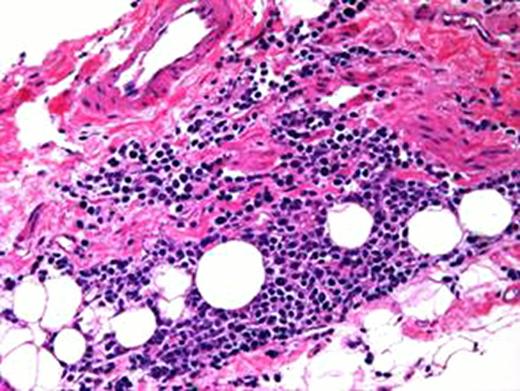

She failed to respond to various agents including corticosteroids and therapeutic plasmapheresis and died 44 days after the single CFZ dose. Repeat serum myeloma markers showed response to CFZ. Autopsy examination revealed TMA with presence of red blood cell fragments and multiple fibrin thrombi in the kidneys without evidence of amyloidosis or plasma cell infiltration. Aggregates of CD 138 positive plasma cells were present in the visceral pleura of the stomach, bladder, pancreas and intestines but without organ infiltration. The bone marrow was hypercellular with 5% involvement with lambda predominant plasma cells. At death, the serum levels of lambda light chains and IgG were 54. 8 and 1000 mg/dL, respectively.

Right kidney TMA at x20